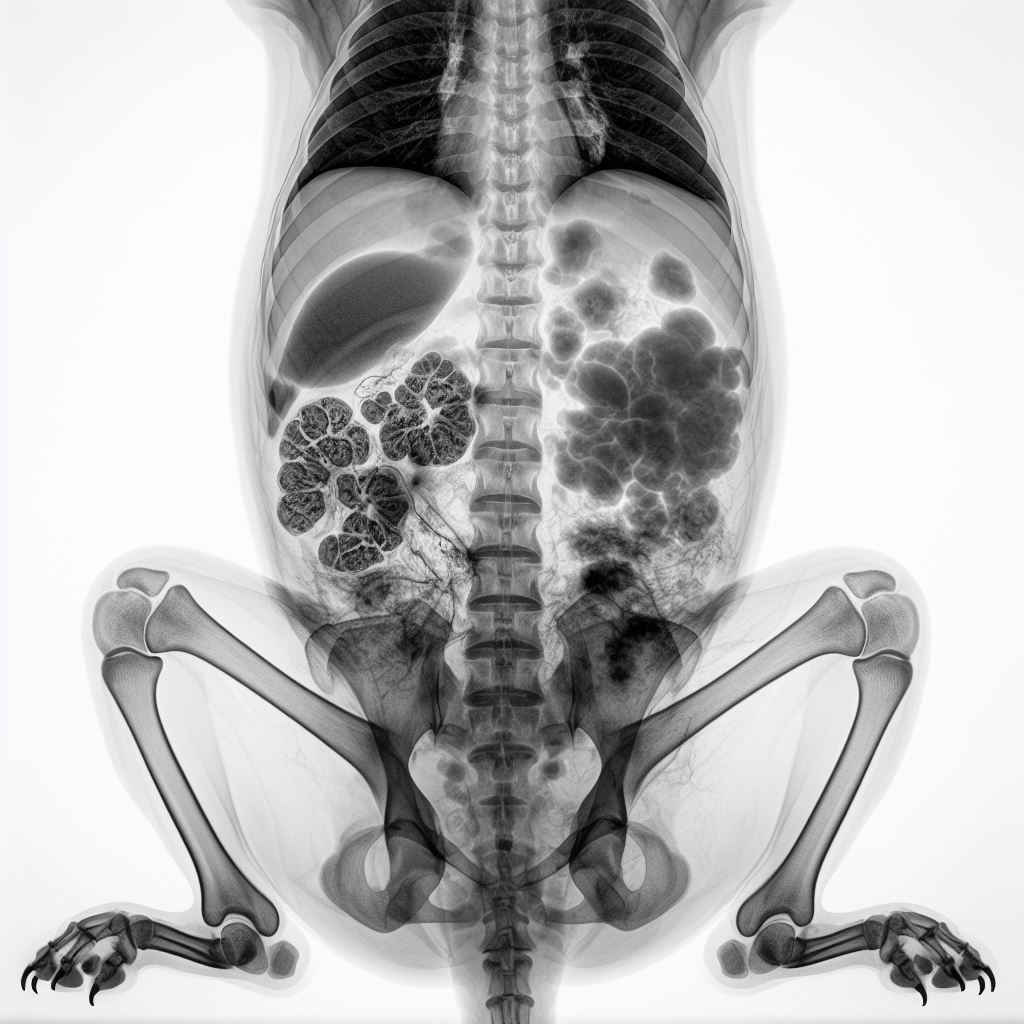

영상 진단 방법 (X-레이, 초음파)

췌장염의 진단에는 영상 진단 방법이 널리 사용됩니다. X-레이와 초음파는 강아지의 내부를 시각적으로 확인할 수 있는 도구로, 췌장의 크기와 모양, 그리고 주변 구조의 이상 여부를 확인하는 데 매우 유용합니다. 이러한 영상 진단 방법은 췌장염의 정도를 평가하는데 도움이 되며, 진단의 정확성을 높입니다. 또한, 영상 진단은 증상이 있는 강아지의 내부 상태를 직접 확인하고, 문제가 발생한 부위를 정확히 파악하는데 중요한 역할을 합니다.